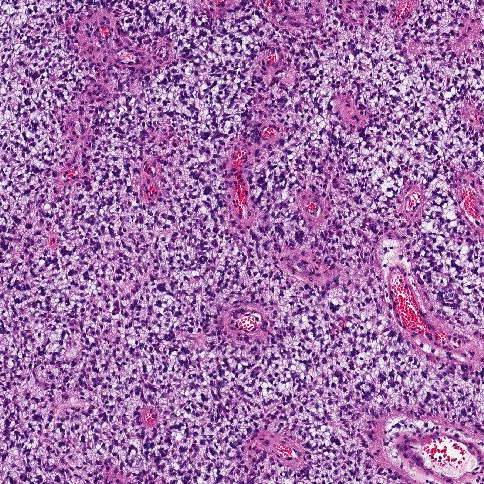

Иммуногистохимия (ИГХ)

Иммуногистохимия (ИГХ) — это важный метод диагностики, который используется для изучения биологических характеристик опухоли, включая экспрессию специфических белков, что помогает уточнить диагноз и определить возможные мишени для терапии.

Роль иммуногистохимии при DIPG:

Иммуногистохимия позволяет визуализировать наличие специфических белков в тканях опухоли с помощью антител, меченных красителями. Это помогает:

1. Подтвердить диагноз DIPG.

2. Определить молекулярные характеристики опухоли.

3. Выявить потенциальные мишени для таргетной терапии.

Основные маркеры, исследуемые при DIPG:

Процесс проведения иммуногистохимии:

Забор ткани:

• Биопсия опухоли (обычно стереотаксическая) проводится для получения образца ткани.

Подготовка срезов:

• Ткань фиксируется и нарезается на тонкие срезы.

Окрашивание:

• Срезы обрабатываются специфическими антителами, которые связываются с целевыми белками.

Анализ:

• Под микроскопом оценивается наличие и интенсивность окрашивания, что указывает на уровень экспрессии маркеров.